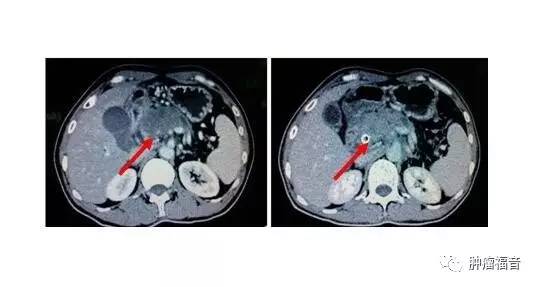

1、黄疸是胰腺癌晚期患者的重要症状,而阻塞性黄疸是胰头癌的最突出表现,发生率在90%以上。而早期胰体、胰尾可无黄疸。黄疸通常呈持续性且进行性加深。完全梗阻时,大便可呈陶土色,皮肤黄染可呈棕色或古铜色,伴瘙痒。